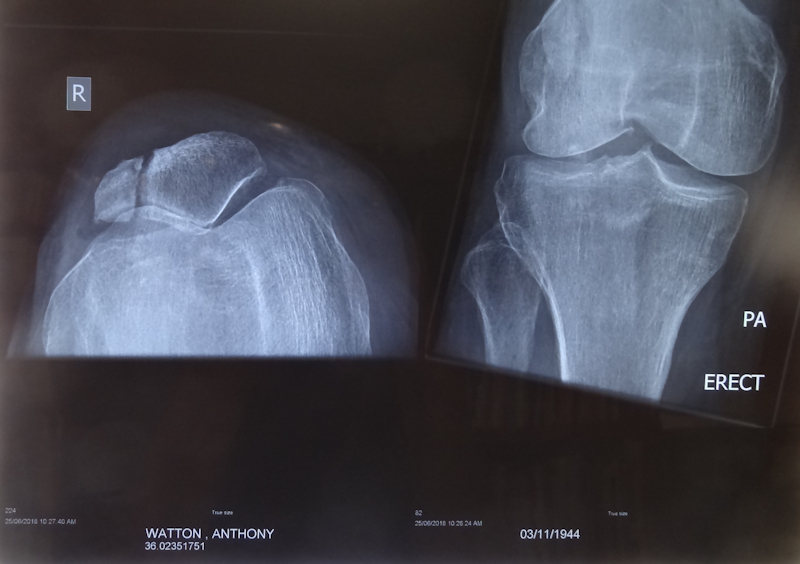

As a result, we initially planned this ride to take place in April 2018 but, following a bike fall in March 2018 in which I suffered a vertical split in my right patella and injured my right wrist and elbow, that ride never happened. The view on the left side of the xray image is from a vertical position. The surgeon said the gap was being filled by scar tissue and he did not operate.